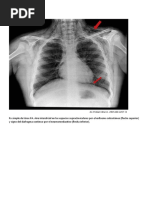

8. Opacidad de un hemitrax.

Lo vas a observar cuando existe atelectasia de todo el pulmn

(unilateral), derrame pleural masivo, neumona que compromete a

todo el pulmn o en casos que haya habido neumonectoma. Es un

signo que nos habla de compromiso pulmonar severo en el

paciente.

Opacidad del hemitrax derecho